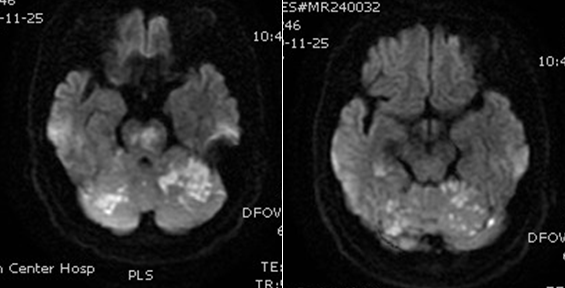

入院影像检查

导丝怎么扩【载药时代 球扩天下】NOVA DES®颅内药物洗脱支架在基底动脉近端重度狭窄的应用—西安市中心医院使用体会一例!_https://www.jmylbn.com_新闻资讯_第4张

MRA

导丝怎么扩【载药时代 球扩天下】NOVA DES®颅内药物洗脱支架在基底动脉近端重度狭窄的应用—西安市中心医院使用体会一例!_https://www.jmylbn.com_新闻资讯_第5张

DWI

重要影像结论:双侧小脑半球、脑干、右侧枕叶多发脑梗死;基底动脉、右侧大脑后动脉闭塞。